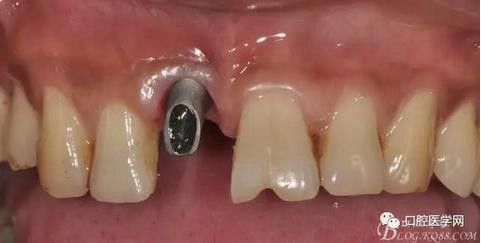

圖19 口內(nèi)修復(fù)基臺正位照

圖20 口內(nèi)修復(fù)基臺正位照